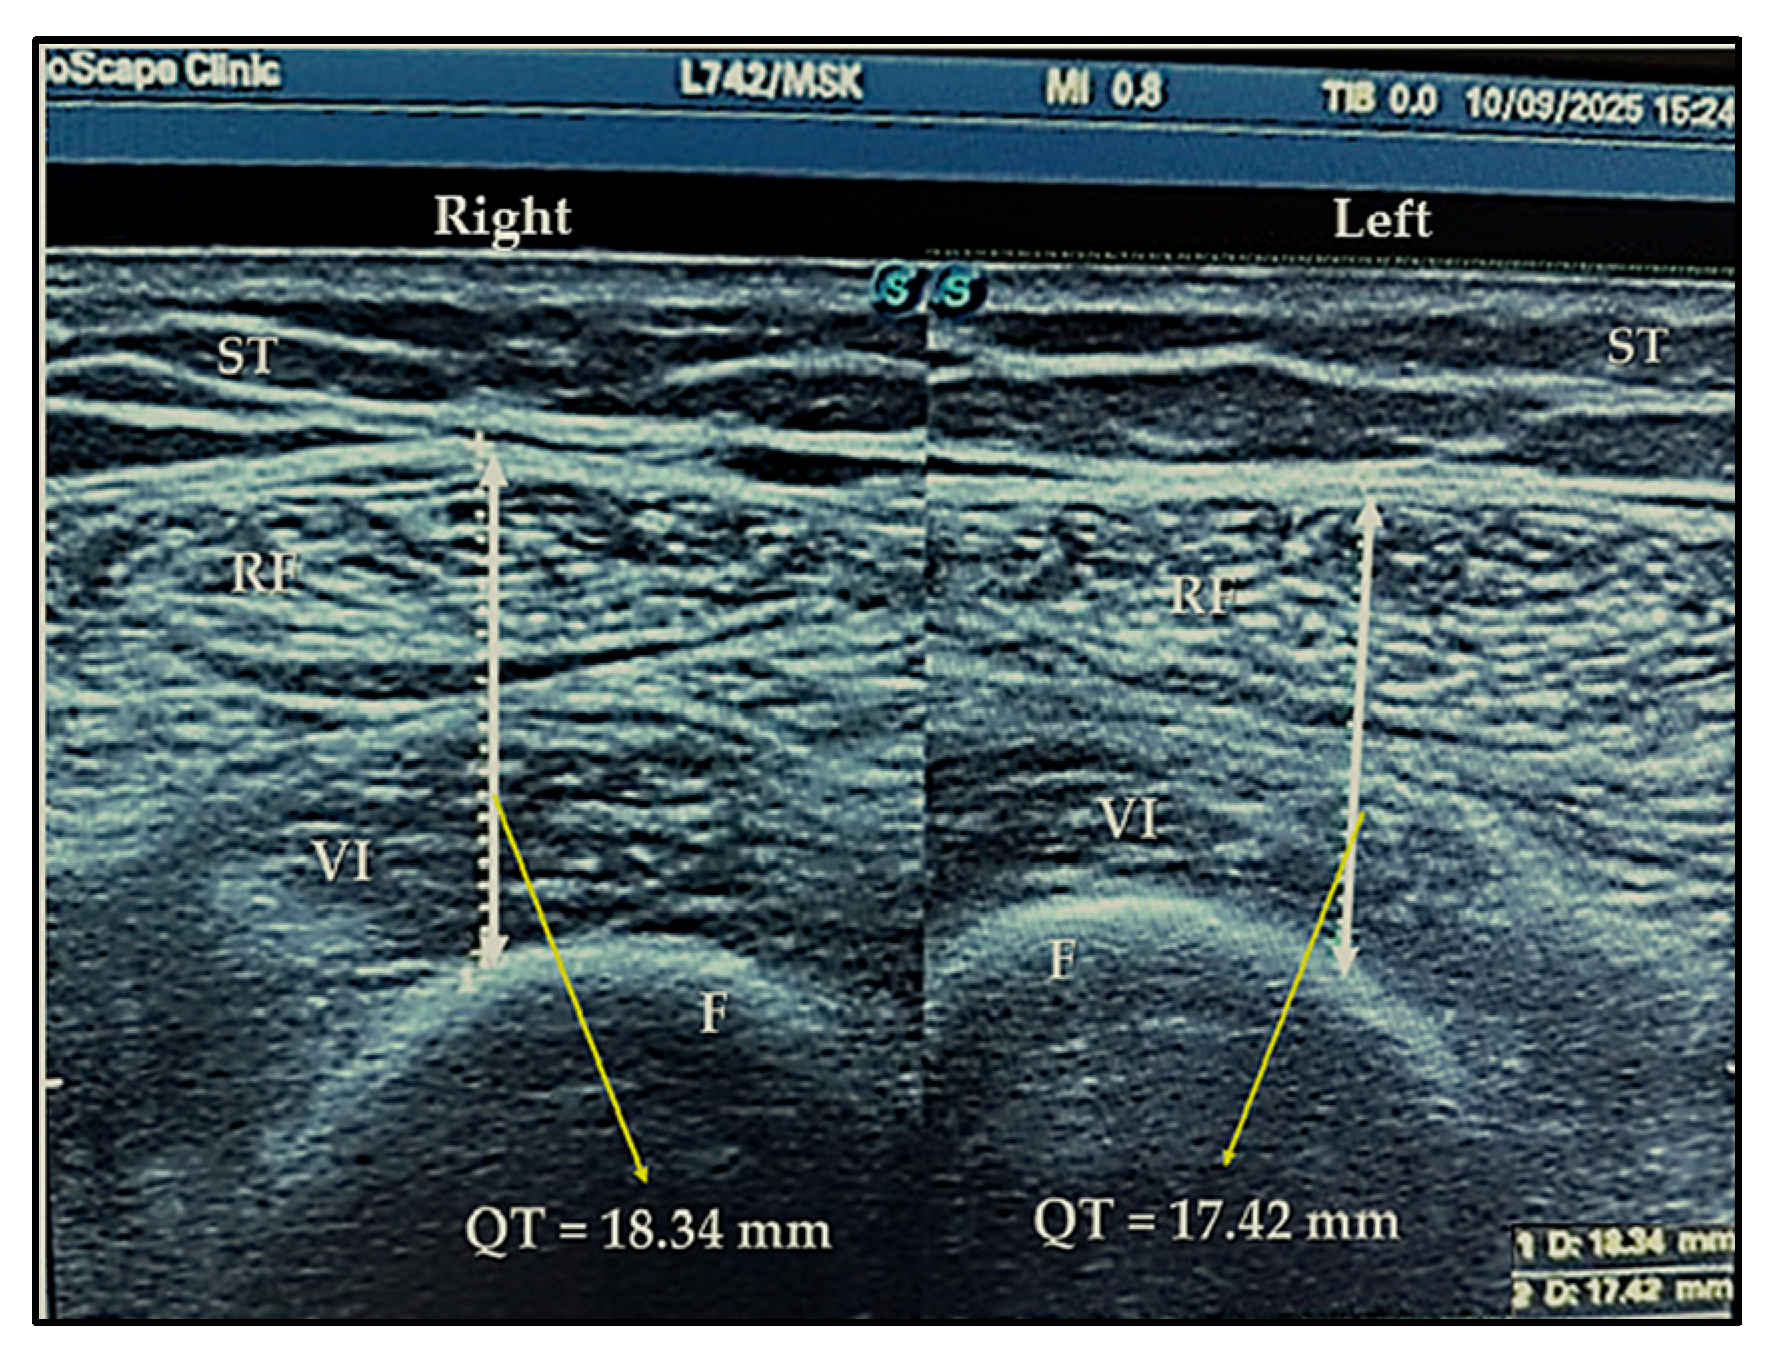

4.2. Ultrasound Exam

| QHNI | height-normalized quadriceps thickness index |